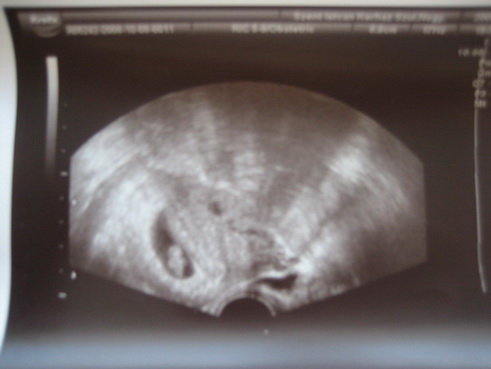

Én anno jártam ahhoz a dokihoz aki írta a könyvet. Valószínű kismamáknak jól tud segíteni: egy ismerősöm mondta hogy 36. hétig nem fordult meg a babája, farfekvéses volt és járt a dokihoz és végülis megfordult. Én ugye azért jártam hogy teherbe essek. Tulképp rengeteg pénzem elment rá és minden egyes alkalom ugyanarról szólt. Szerintem otthon nyugodt körülmények között mindenki el tud lazulni és tud beszélgetni a babájával. (Ha gondolod küldök privit.) El kell képzelni az ottani környezetet, ahol most a baba van. Most hétfőn amikor voltam uh-n, mondtam a babáimnak hogy mutassák meg magukat és meg is mutatták: mindkettő mocorgott és nagyon nagy élményben részesítettek.